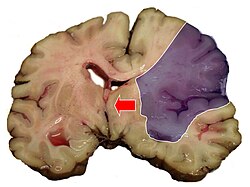

Der ischämische Schlaganfall oder Hirninfarkt (veraltet „weißer Schlaganfall“) ist eine neurologische Erkrankung durch plötzliche Minderdurchblutung und daraus folgende Minderversorgung des Gehirngewebes. Die Minderdurchblutung wird meist durch Einengung oder Verschluss einer oder mehrerer hirnversorgender Arterien verursacht. Selten sind Venenverschlüsse die Ursache. Der ischämische Schlaganfall ist die häufigste Form des Schlaganfalls.

Unterschreitet der zerebrale Blutfluss bzw. die Energiezufuhr die so genannte Funktionsschwelle, stellen die Hirnzellen ihre aktive Funktion zunächst reversibel ein. Es kommt zur Ischämie. Dieser Zustand kann jedoch nur eine bestimmte Zeit aufrechterhalten werden. Bei länger anhaltender Ischämie entsteht ein Infarkt, da die Zellstruktur nicht länger erhalten werden kann. Sinkt der zerebrale Blutfluss bzw. die Energiezufuhr weiter und unter die so genannte Infarktschwelle, werden die Hirnzellen ebenfalls irreversibel geschädigt und sterben ab, so dass ein Infarkt entsteht.

- Ein primär ischämischer Infarkt kann sekundär einbluten. Dies zeigt sich klinisch meist als Zweitereignis. In einem solchen Fall geht man therapeutisch wie bei einer intrazerebralen Blutung vor.